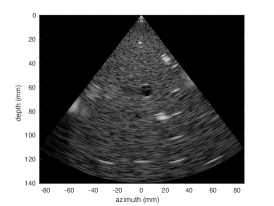

3.2 Results

Quantitative results for the cardiac test set are summarized in Table 1. We show a major improvement in decorrelation and SSIM for both and MLA. The corrected MLA performance approaches that of MLA, suggesting the feasiblity of larger MLA factors. Figure 4 shows representative images from each imaging modality. We show that the correlation coefficients profile of the corrected and MLA approaches that of SLA.

![]() |

|

| (a) SLA | (b) MLA | (c) Corrected MLA | |

||

|||

| (d) MLA | (e) Corrected MLA |